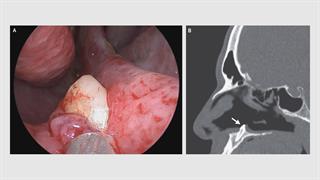

Γιατροί ανακάλυψαν δόντι που αναπτύχθηκε στο ρουθούνι ασθενούς

Πρώτα βρήκαν απόκλιση του διαφράγματος με ρινοσκόπιο και ανακάλυψαν ένα άσπρο αντικείμενο να προεξέχει από το τοίχωμα του δεξιού ρουθουνιού.